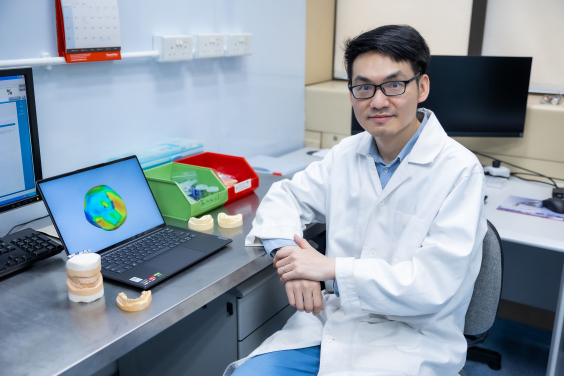

Project co-investigator Dr Hao Ding and the design of a personalised tooth crown using generative AI.

The researchers developed a generative AI algorithm that uses a true three-dimensional (3D) deep learning approach, producing personalised dental crowns with high accuracy that mimic the morphology and match the materials required for the biomechanics of natural teeth. Biomechanical finite element analysis revealed that by using lithium silicate, the AI-designed crown can come very close to achieving the expected lifespan of natural teeth. In contrast, the two existing methods of designing dental crowns result in crowns that are either too large or too thin, and fall short of matching the same lifespan as natural teeth.

The results have been published in leading academic journal Dental Materials in an article titled ‘Morphology and mechanical performance of dental crown designed by 3D-DCGAN’.

“We used a 3D-DCGAN (3D-Deep Convolutional Generative Adversarial Network) approach to ‘teach’ the AI algorithm ‘good’ designs by feeding the algorithm with over 600 cases of natural and healthy dentition. The algorithm improves the quality of the design through internal competition between a generator and a discriminator,” said Dr Hao Ding, a co-investigator on the project.

The 3D-DCGAN AI-designed crowns were compared with natural teeth and with two other conventional CAD methods of crown design methods. The results revealed that the generative AI-designed crowns had the lowest 3D discrepancy, closest cusp angle (morphological feature), and similar occlusal contacts (functional feature) as compared to natural teeth.